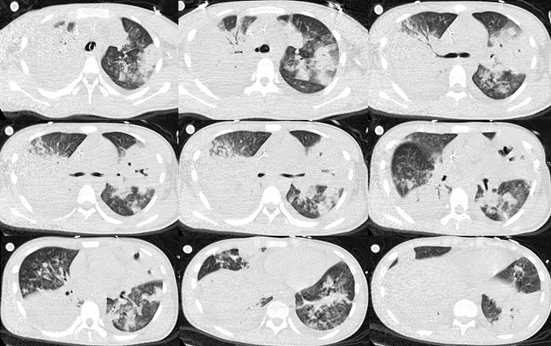

影像学(20181月31):沿支气管血管束分布的斑片影,部分出现空洞,胸膜下实变影。

图片

根据患者早期症状和检查结果,启动了经验性抗真菌治疗。根据3天后回报的BALF GM试验阳性结果诊断为IAA。抗真菌治疗2周后,复查胸部CT可见病灶较前明显吸收,最终患者康复出院。我们总结此例患者治疗有效的经验,是早期即根据患者症状、实验室检查和影像学表现诊断了IAA,缩短了患者从起病至治疗的时间。